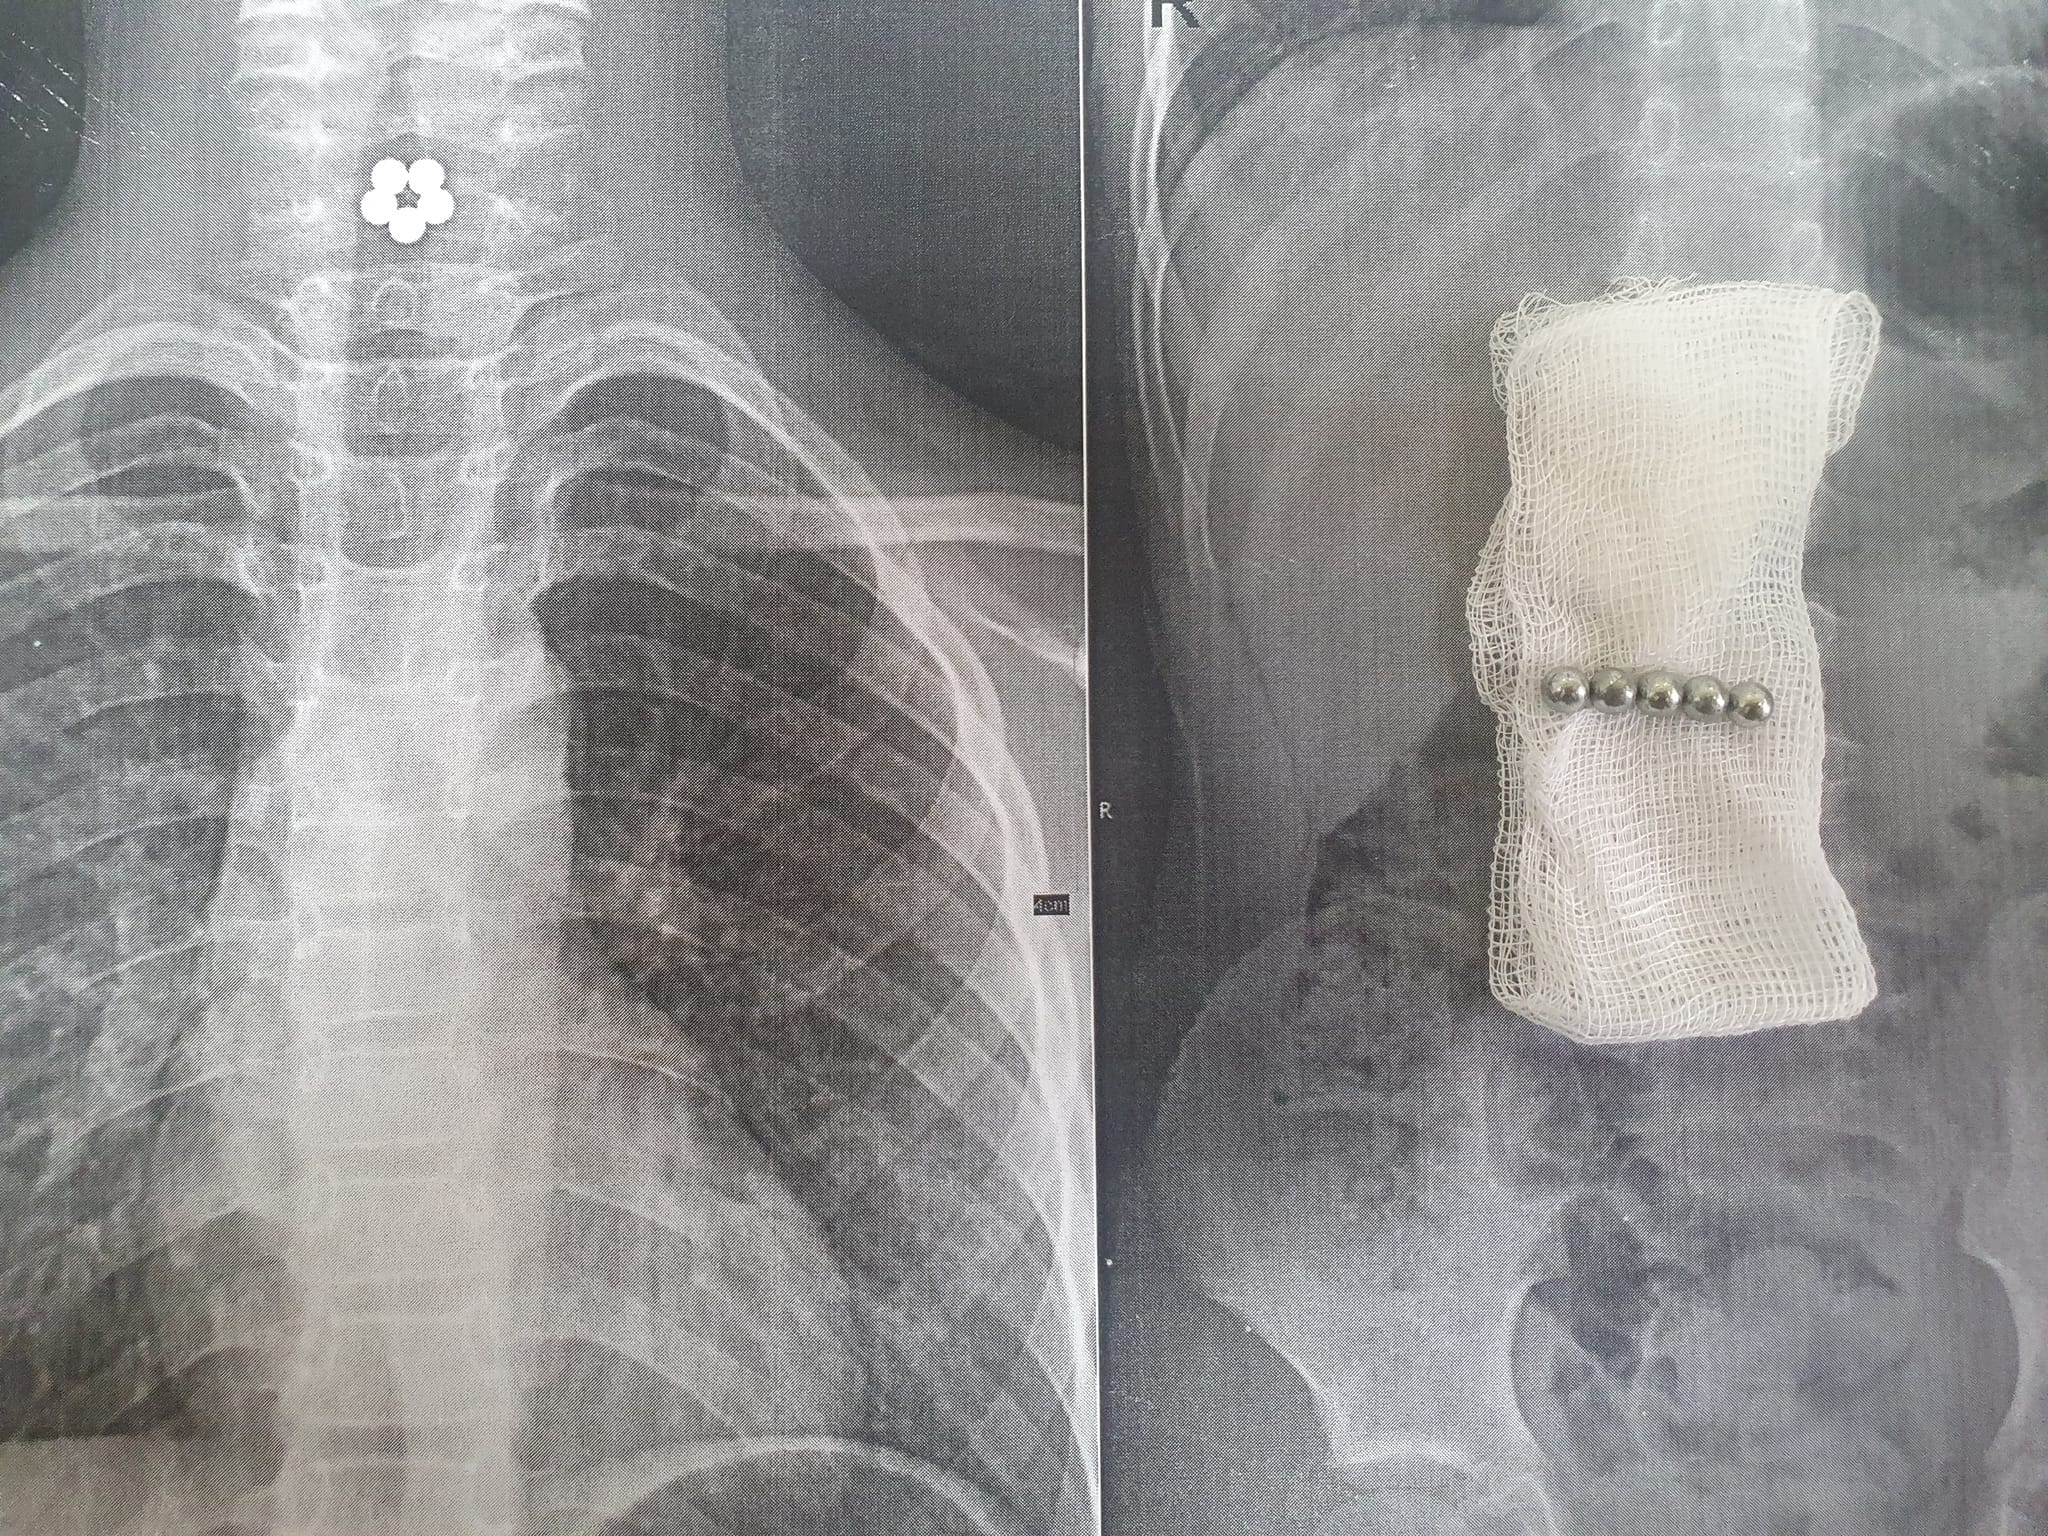

У львівську лікарню госпіталізували семирічну львів’янку, яка випадково проковтнула п’ять магнітиків. Дитина задихалася і відчувала дискомфорт у шиї.

Магнітики затрималися у стравоході і склалися в квіточку. Дитина вдома починала задихатися, її турбував дискомфорт у шиї і батьки терміново викликали швидку допомогу.

Коли дитину привезли в лікарню, їй зробили рентген і, аби не допустити потрапляння магнітів у кишківник, що могло викликати перфорацію його стінок, хірурги одразу ж за допомогою сучасного інструментарію ­(щипці Karl Storz) під контролем оптики, дістали магніти із стравоходу.